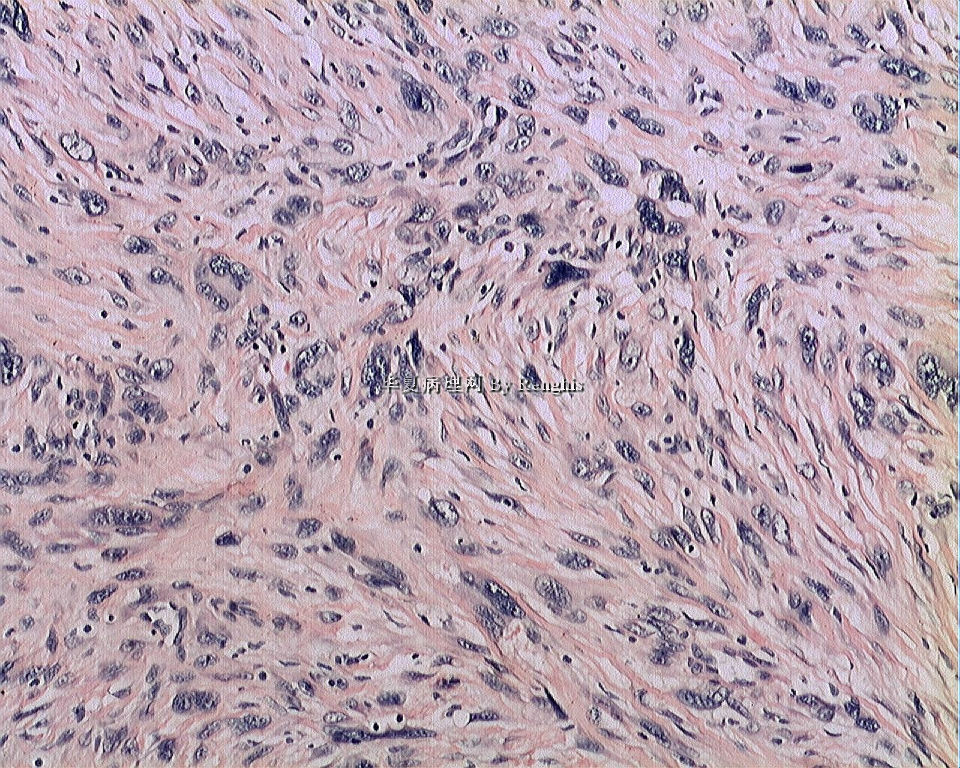

女,29岁,左大腿内侧肿物直径2.8cm,切面灰白、实性、质中,似有包膜。

本例就形态学而言不太符合纤维肉瘤,对于一个多形性和异型明显的肿瘤首先不考虑纤维肉瘤的诊断加上车辐状结构首先还是考虑纤维组织细胞肿瘤。

本人认同此例是一例比较典型的纤维肉瘤,瘤细胞程束状、鱼骨状及编织状排列,部分瘤细胞异型性明显,免疫组化vimentin阳性,SMA灶状弱阳性,desmin阴性,S100阴性,CK阴性,EMA阴性,余记不得了,明天看看再上传。